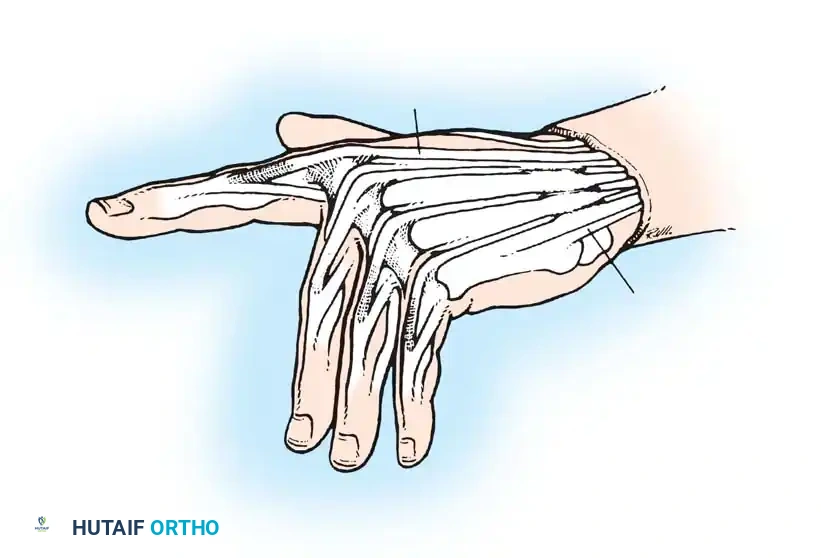

Correction of PIP Hyperextension Deformity (Beckenbaugh FDS Tenodesis)

This technique utilizes a slip of the FDS to create a volar tether, preventing PIP hyperextension while allowing active flexion.

Incision and Exposure: Make a volar zigzag (Bruner) incision over the middle and proximal phalanges. Meticulously avoid damaging the digital neurovascular bundles, which may be displaced or adherent to the cruciate pulley system anterior to the hyperextended PIP joint.

Volar zigzag incision providing wide exposure of the flexor tendon sheath. -